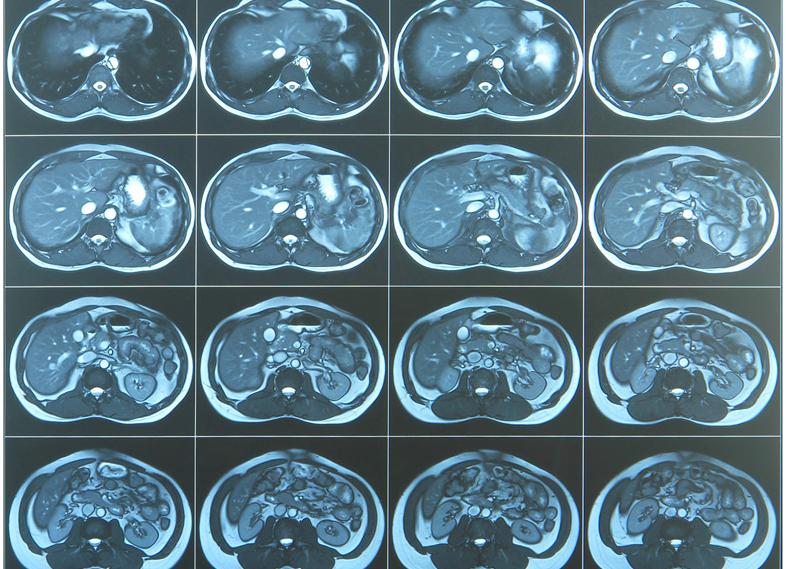

МРТ брюшной полости и забрюшинного пространства

Диагностической целью МРТ забрюшинного пространства является обследование почек, надпочечников, мочеточников, лимфатических узлов, сосудов (крупных артерий, вен и их ветвей), мягких тканей, окружающей клетчатки. В процессе томографии изучают МР-анатомию этих структур, при наличии патологических изменений в органах проводят их оценку.

В МРТ забрюшинного пространства входит изучение почек и надпочечников, сосудов почек (МР-ангиография), лимфатических узлов, оценка МР-сигнала от окружающей клетчатки и мягких тканей. На МР-томограммах производят измерение почек, почечной паренхимы, внутренних полостей (лоханки и чашечек).